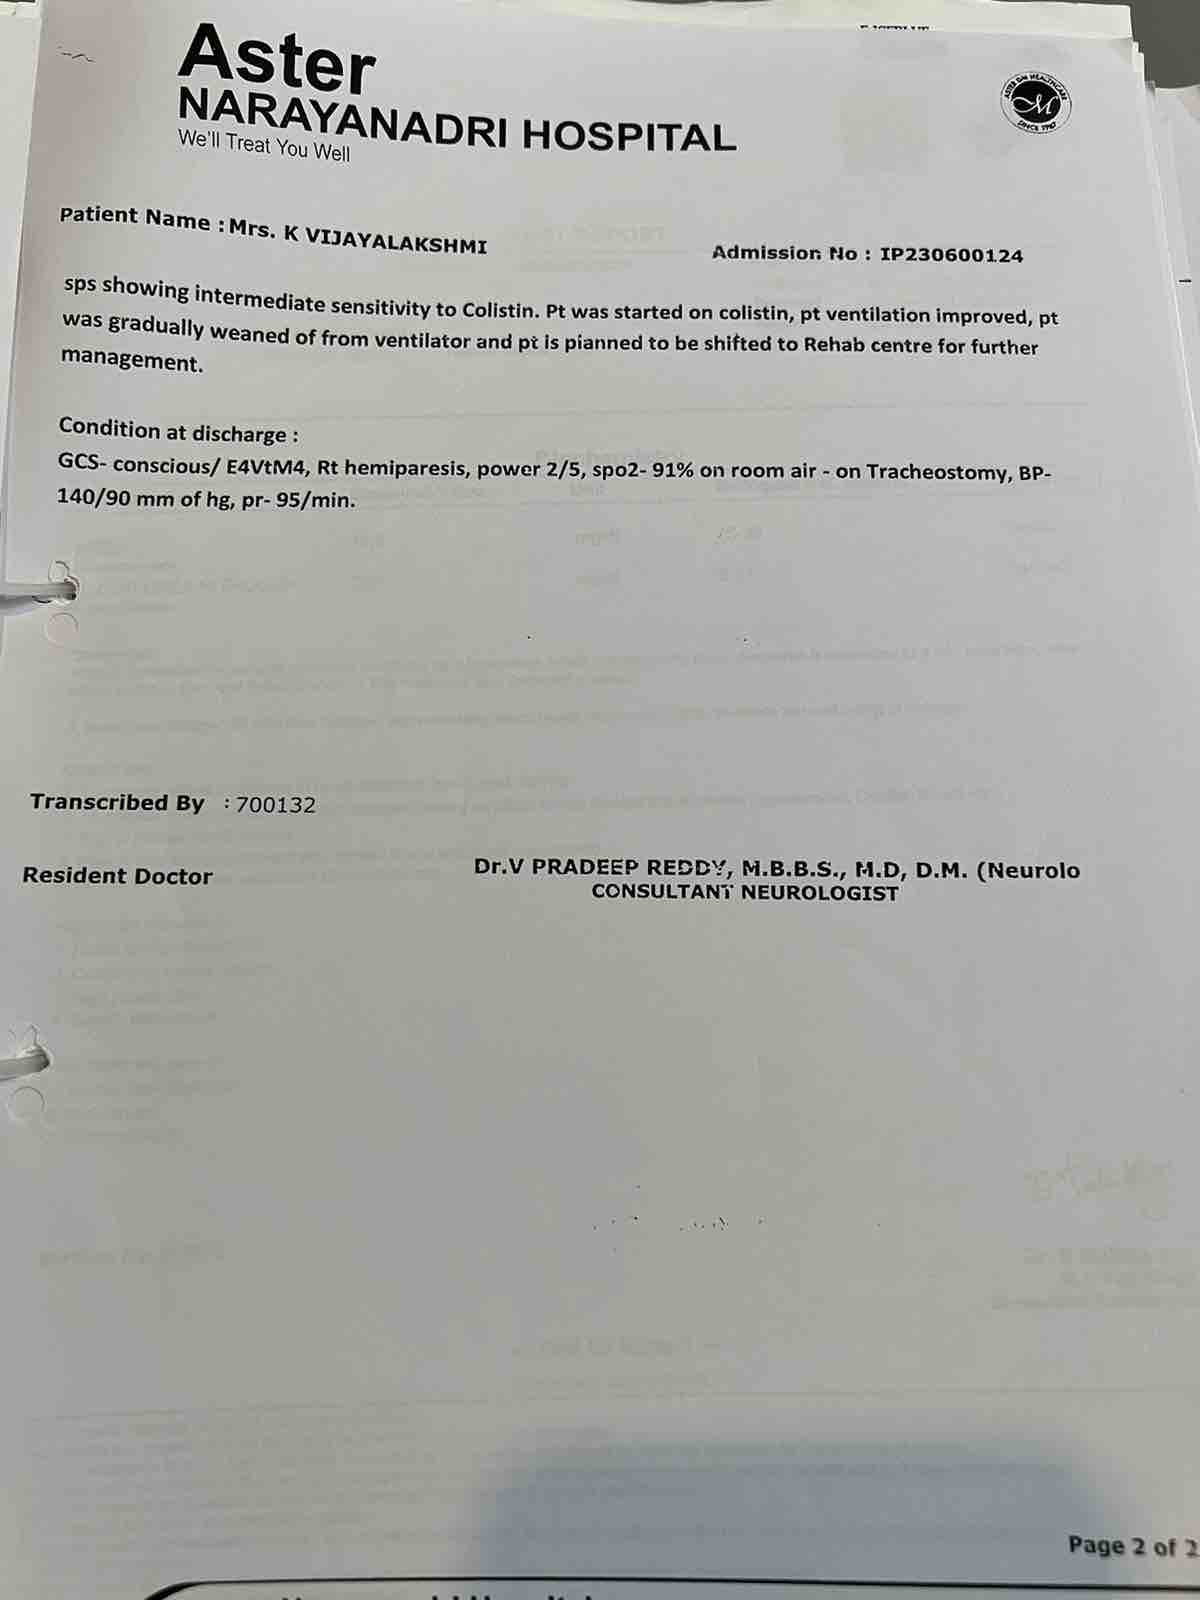

We are reaching out to you today with a heavy heart and a plea for help. Our beloved 66-year-old mother K VIJYA LAKSHMI, has been facing an incredibly challenging journey since 16th May when she had brain stroke & underwent emergency brain and abdomen surgery. Her recovery has been a rollercoaster of ups and downs.

During her hospitalization, she endured multiple complications, including respiratory distress, recurrent severe infections, and even seizure-like activity. Through it all, she has shown immense strength and determination. Still she require three more surgeries to stand on the path of recovery.